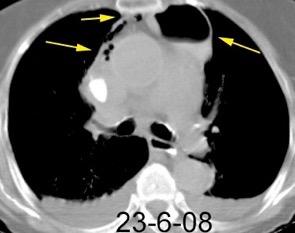

Ganglios retroperitoneales (flechas negras)

germinales del testículo izquierdo Nódulos pulmonares múltiples. (flechas verdes). Ganglios paratraqueales. (flechas amarillas). Dudoso ensanchamiento retrocrural (flechas negras)

Panda A et al. “Straddling Across Boundaries”. Thoracoabdominal Lesions: Spectrum and Pattern Approach. Curr Probl Diagn Radiol, 2015